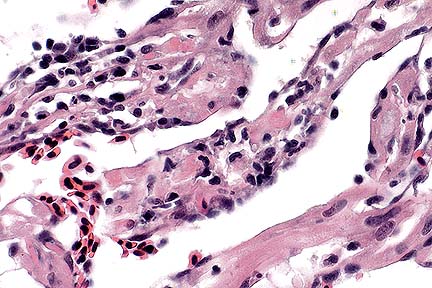

Non suppurative meningoencephalitis in an Appaloosa gelding infected with equine lentivirus (HE, 100X, 76K)

Perivascular cuffing of a cerebellar blood vessel with moderate nubmers of lymphocytes and lesser numbers of macrophages and plasma cells in a horse infected with equine lentivirus. (HE, 400X, 45K)

Contributor's Diagnosis and Comments: Severe nonsuppurative meningoencephalitis and choroid-plexitis with microgliosis. Lentivirus of equine infections anemia (EIA).

This case represents a classic presentation of the neural form of EIA. In the contributors experience, less than 2% of Coggin's positive horses have evidence of CNS involvement. This horse had typical gross lesions of recrudescing EIA. The farm of origin has had problems in the past with EIA and this case caused a quarantine to be placed on the farm.

The CNS lesion typically has an "inside out" pattern, whereby the inflammation is severe around the ventricular system. In this horse, that was best seen in the spinal cord. This horse tested negative for sarcocystosis, neosporsosis, VEE and EEE.

AFIP Diagnosis: Cerebellum, brain stem, midbrain, and choroid plexus: Choriomeningoencephalitis, nonsuppurative, multifocal, moderate, Appaloosa, equine.

Conference Note: Equine infectious anemia affects horses, mules, and donkeys. It is caused by a lentivirus in the family Retroviridae. The virus is spread by arthropods, which serve as mechanical rather than biologic vectors. The disease can also be spread by contaminated needles, syringes, tattoo equipment, or experimentally, by the administration of infected blood or the virus. The virus primarily infects cells of the monocyte-macrophage system; however, in the acute viremic stage, viral DNA is also found in cells of the liver, lymph nodes, bone marrow, spleen, and kidney. Equine infectious anemia causes intracellular hemolysis followed by immunoproliferation and finally by hematopoietic, and to a lesser extent, immune exhaustion. It is believed that the EIA virus does not directly kill cells and that the cellular damage is the result of indirect effects of the immune response. The clinical signs of EIA develop at the time of the appearance of circulating antibody which is complement fixing. C3 adheres to erythrocyte membranes, stimulating macrophage recognition and erythrophagocytosis. This results in severe intravascular hemolysis and anemia.